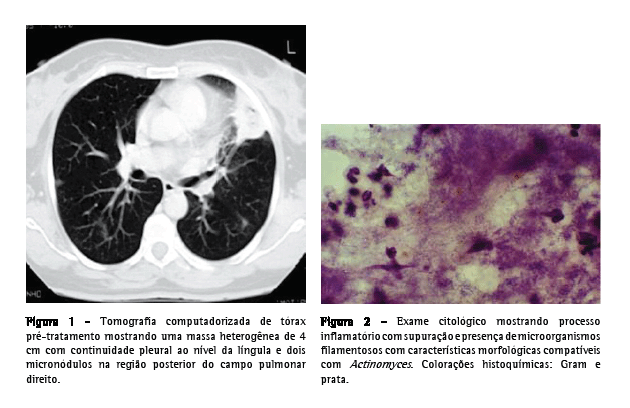

Relato do casoUma paciente do sexo feminino, 55 anos de idade, caucasiana, não fumante, secretária, procurou atendimento no serviço de emergência. Tinha história de hepatite B crônica, hipertensão arterial, dislipidemia mista e múltiplas cáries dentárias não tratadas. Relatou que há três semanas havia iniciado quadro de dejeções diarréicas diárias, azia, desconforto retroesternal agravado pelo decúbito dorsal, astenia, anorexia e emagrecimento (5 kg). Uma semana depois haviam surgido toracalgia esquerda de características pleuríticas com agravamento progressivo, acessos freqüentes de tosse seca ao esforço e pico febril isolado. O eletrocardiograma foi normal, e a endoscopia digestiva alta revelou um cárdia complacente e gastrite antral. A telerradiografia de tórax mostrou hipotransparência heterogênea, esboçando perda de substância em seu seio, no terço médio do campo pulmonar esquerdo. A tomografia computadorizada de tórax evidenciou a presença de uma massa de 4 cm com conteúdo heterogêneo e continuidade pleural ao nível da língula e a presença de dois micronódulos subpleurais na região posterior do campo pulmonar direito (Figura 1). Procedeu-se ao estudo etiológico considerando-se a hipótese diagnóstica de neoplasia pulmonar como a mais provável. Do estudo analítico, salientam-se os seguintes resultados: velocidade de hemossedimentação = 98 mm/1a h; antígeno do câncer 125 = 63,3 U.mL-1 (<35,0); antígeno carcinoembriogênico = 3,55 ng.mL-1 (<2,5) e discreta elevação da proteína C reativa. O estudo imunológico sérico, os marcadores virais e o estudo analítico final não revelaram outras alterações relevantes. Os resultados da colonoscopia, da ultrassonografia abdominopélvica, da mamografia e da citologia cérvico-vaginal foram normais. A primeira fibrobroncoscopia realizada mostrou sinais inflamatórios difusos ao nível da língula. Os resultados do exame citológico de aspirado, lavado brônquico e lavado broncoalveolar foram negativos para células neoplásicas. O exame microbiológico em aerobiose foi também negativo, assim como a pesquisa de bacilos álcool-ácido resistentes. A paciente foi então submetida à biópsia aspirativa transtorácica (BAT), que, ao exame citológico extemporâneo, mostrou um processo inflamatório com supuração. Face a este resultado provisório, iniciou-se a antibioticoterapia com levofloxacina 500 mg via oral ao dia, e decidiu-se realizar uma segunda fibrobroncoscopia. Entretanto, o exame citológico da BAT revelou aspectos morfológicos compatíveis com a presença de Actinomyces, confirmada pelo exame microbiológico cultural do lavado brônquico e broncoalveolar da segunda fibrobroncoscopia, no qual se identificou A. naeslundii (Figura 2). A pesquisa de bacilos álcool-ácido resistentes foi negativa. Dada a melhoria clínica e radiológica após um mês de tratamento (Figura 3), optou-se por manter a antibioticoterapia já iniciada, cuja posologia foi alterada: levofloxacina 500 mg endovenoso ao dia por quatro semanas e, depois, 500 mg po qd. Não se verificou iatrogenia à terapêutica, a qual foi mantida por 16 semanas, até a completa normalização radiológica. Analiticamente constatou-se uma redução da velocidade de hemossedimentação e uma redução de ambos os marcadores tumorais inicialmente alterados, assim como a normalização da proteína C reativa. A paciente foi também submetida a tratamento dentário.